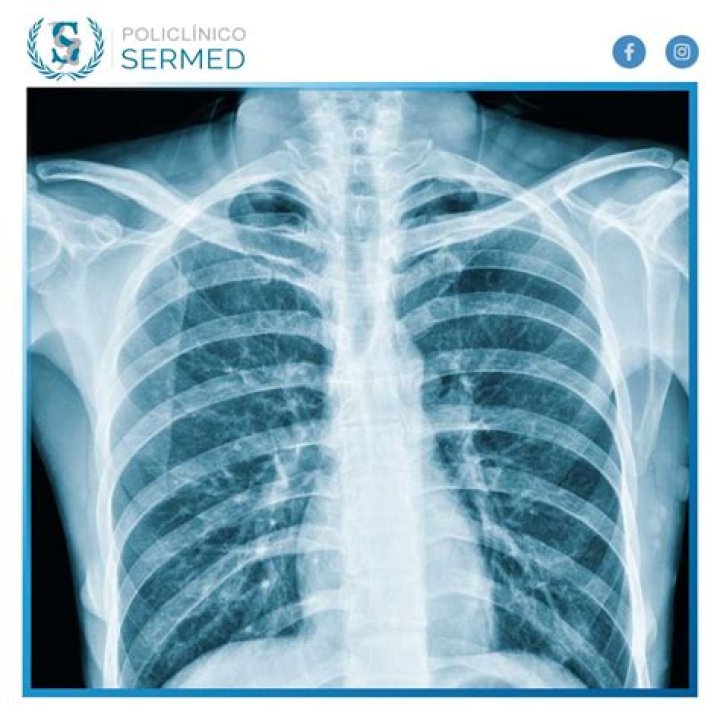

¿Qué incluye el examen del tórax?

La radiografía de tórax es el examen de diagnóstico por rayos X más comúnmente realizado. Una radiografía de tórax produce imágenes del corazón, los pulmones, las vías respiratorias, los vasos sanguíneos, y los huesos de la columna y el tórax.